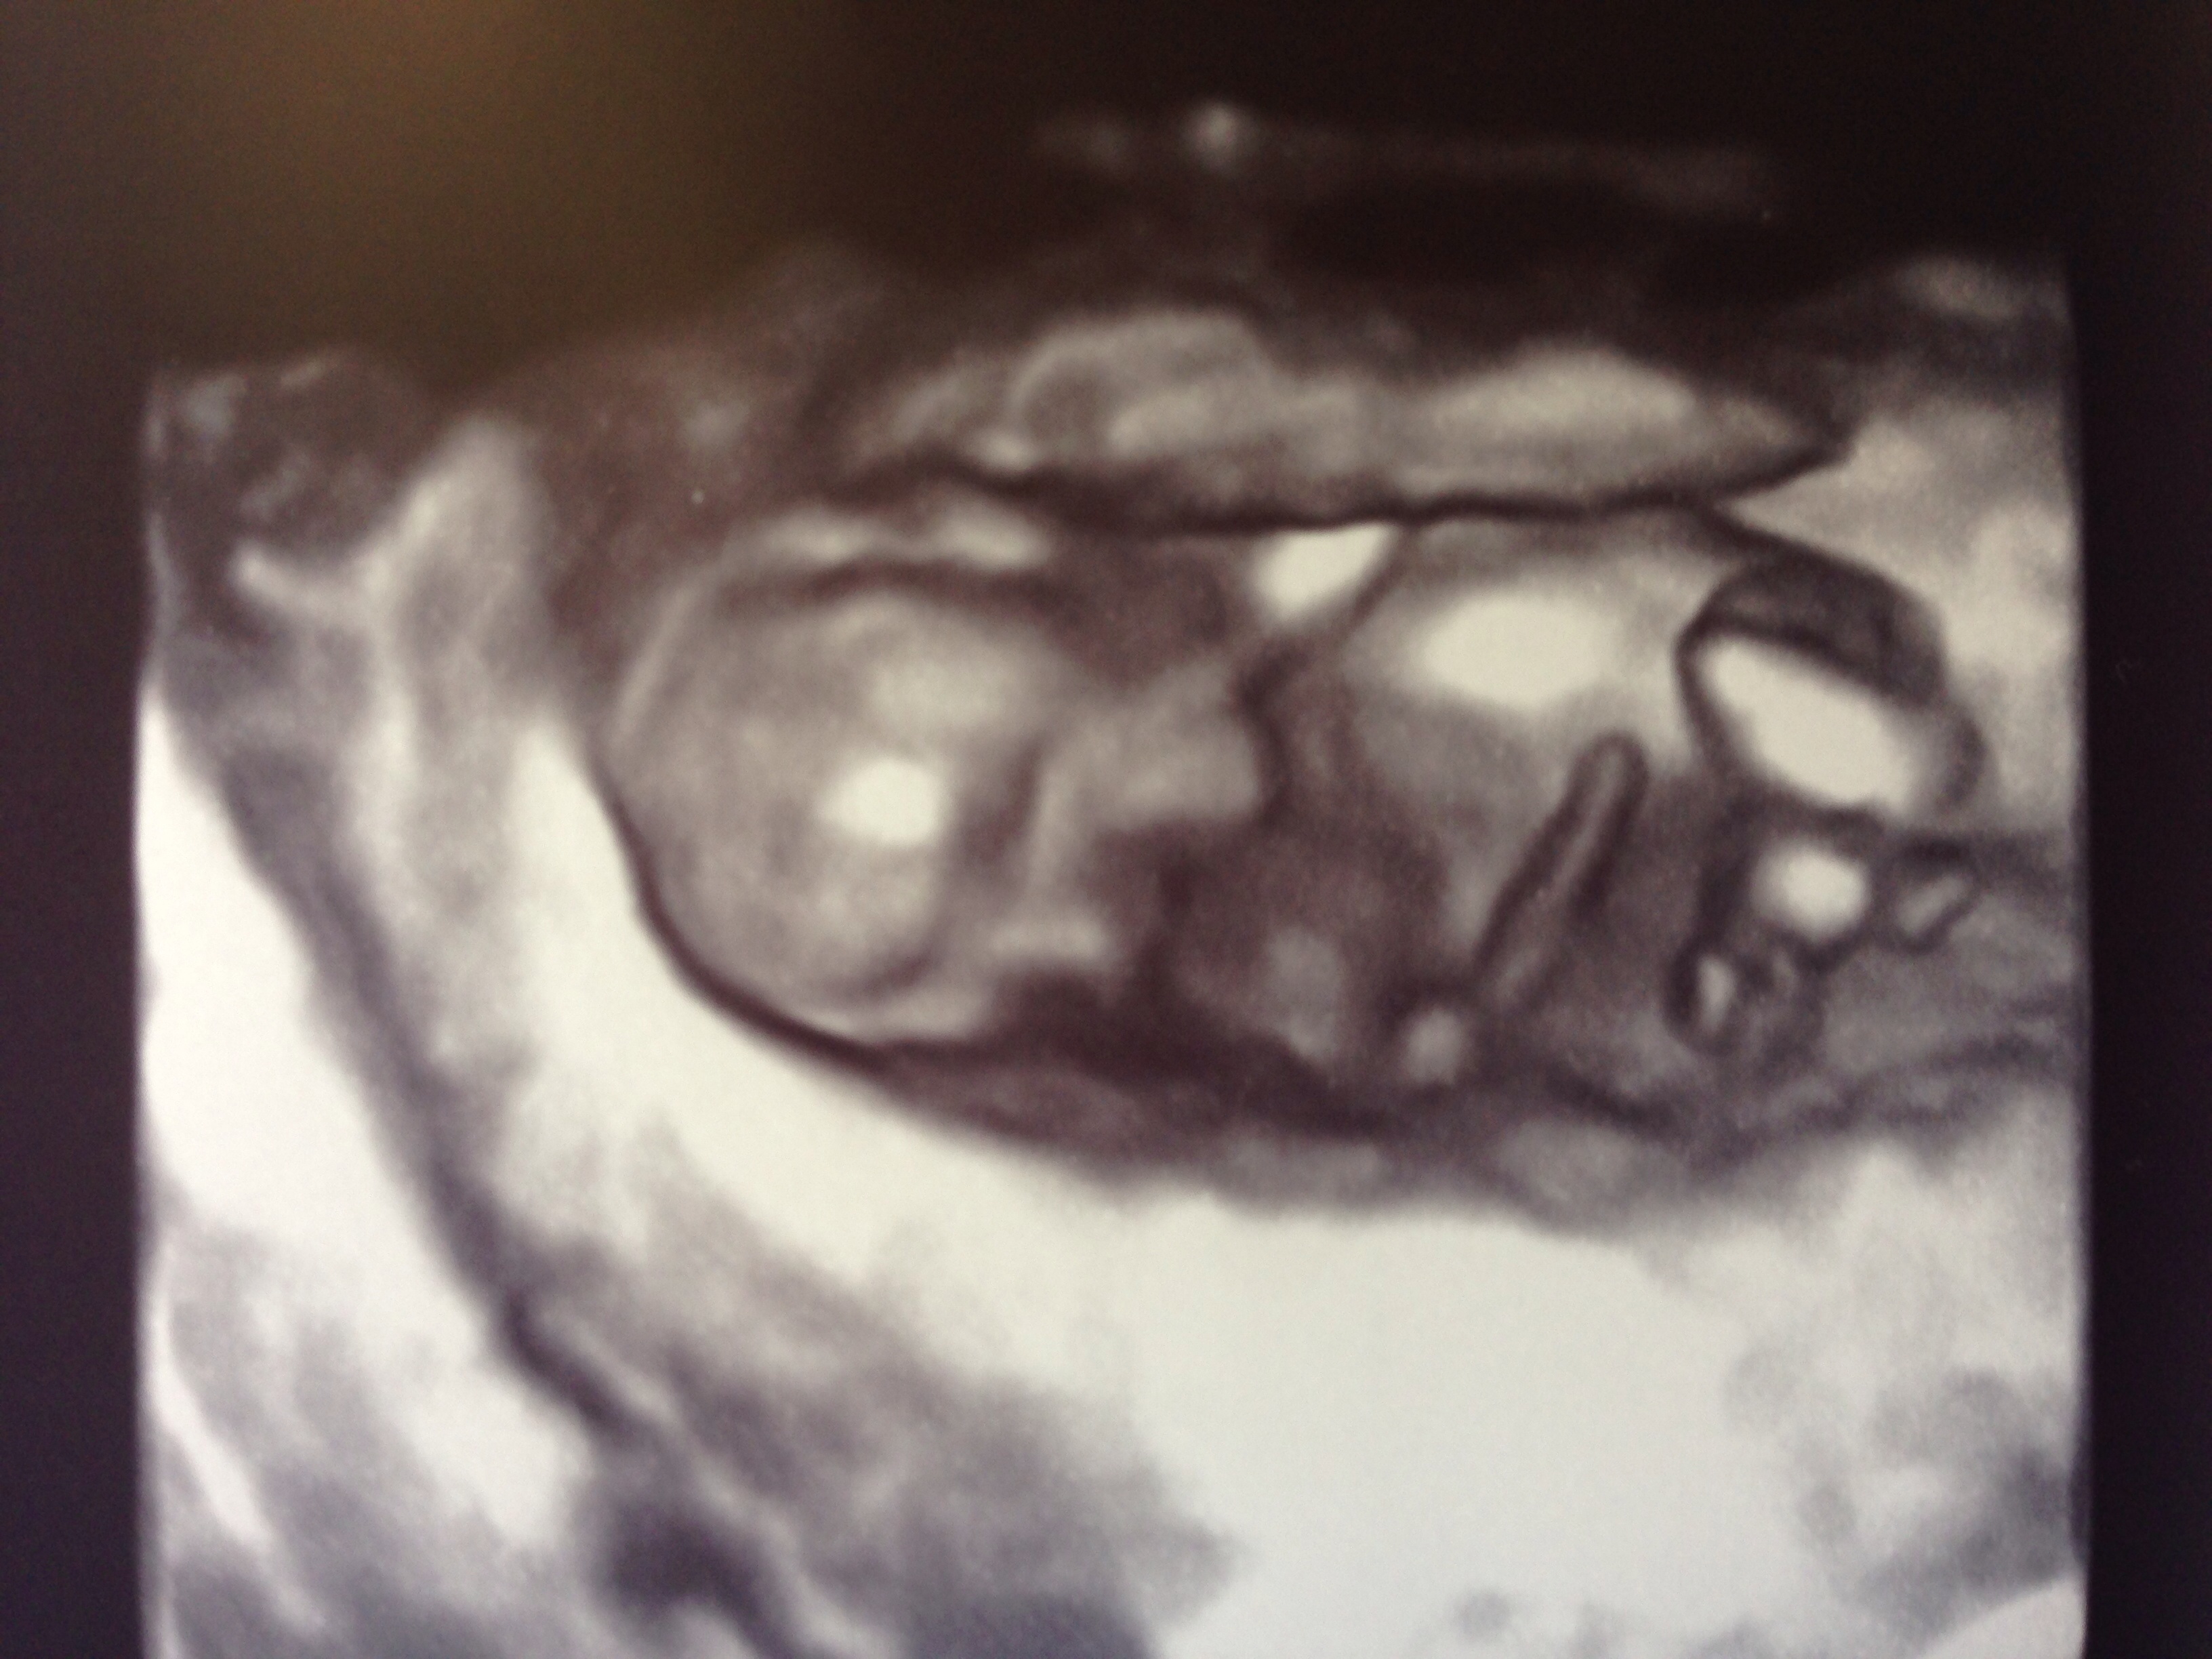

Had my first tri screening this week and it was so great seeing the little baby! I've been feeling fantastic and hoping this continues. I just told my bosses today and we are going to officially announce to Facebook on Saturday. My u/s tech took lots of photos and even tried some in 3D. This was the best so I wanted to share. Hard to see at first but head/nose at top, arm across belly and other arm across face and two little legs bent and you can see a foot on the left.